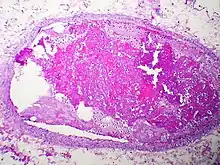

Embolism by other materials is rare. Septic embolism happens when a purulent tissue (pus-containing tissue) is dislodged from its original focus. Tissue embolism is a near-equivalent to cancer metastasis, which happens when cancer tissue infiltrates blood vessels, and small fragments of them are released into the blood stream. Foreign-body embolism happens when exogenous—and only exogenous—materials such as talc enter the blood stream and cause occlusion or obstruction of blood circulation. Bullet embolism occurs in approximately 0.3% cases of gunshot wounds.[8] Amniotic-fluid embolism is a rare complication of childbirth.

Septic emboli may also be a contributor to spreading infection through the bloodstream to other tissues.[11]